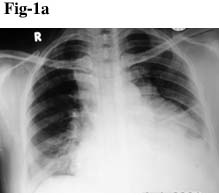

On admission chest radiograph and CT scan were done. Chest X-ray P/A view showed a lobulated opacity in the left mid and lower zones near paracardiac location obscuring the left cardiac border and left hemidiaphragm. Ill-defined opacity was also seen in the right lower zone (Fig. 1a).

Fig 1(a). Chest X-ray P/A view shows the lobulated opacity in the left mid and lower zones.